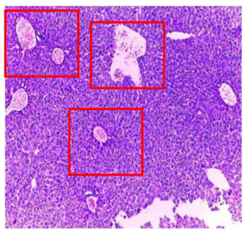

| Organ | T | EA | n-BuOH |

|---|---|---|---|

| Liver | ![]() | ![]() | ![]() |

| Hepatic parenchyma with conserved architecture | Vascular congestion, balonization of cytoplasm with clear nucleus, presence of necrosis, acidophilic bodies, basophils, small hyperchromatic nucleus, lobular lymphocyte filtrate. | ||

| Kidneys | ![]() | ![]() | ![]() |

| Round parenchyma surrounded by a fibro-adipose capsule of preserved architecture | Seat of vascular congestion with lesion of interstitial nephritis mainly made up of lymphocytes dispersed between the tubules and by sectors surrounding glomeruli. There was no objective glomerular damage on the limits of the sectors examined. Presence of surrenal gland with conserved morphology and cytology. | ||

| Lung | ![]() | ![]() | ![]() |

| A pulmonary parenchyma, made of optically empty cavity (alveoli) separated by fibrous septa | Lung parenchyma seat of vascular congestion The vessels have a hyalinised wall with the presence of haemorrhagic diffusion. | Presence of vascular congestion Presence of lymphocytes inflammatory infiltrate | |